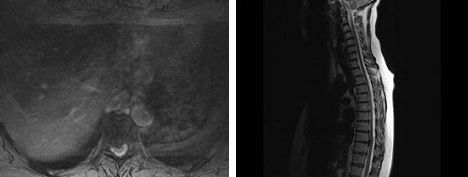

男,65岁,背部疼痛2个月余,MRI检查如图,请选出最可能的诊断()

A:椎间盘炎

B:椎管内肿瘤

C:椎间盘突出

D:硬膜外纤维化

E:神经根鞘囊肿